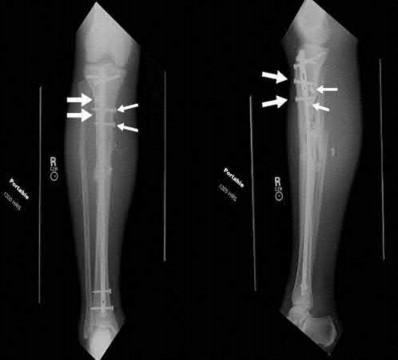

What is the most common type of malalignment after intramedullary nailing of distal 1/3 extra-articular tibia fractures using a infrapatellar approach when compared with plating?

The most common type of malalignment after intramedullary nailing of distal 1/3 extra-articular tibia fractures using an infrapatellar approach when compared with plating is valgus malalignment.

Fixation of distal one-third tibial shaft fractures can be successfully treated with either intramedullary nailing or plating. The literature describes advantages and disadvantages to both approaches, however intramedullary nailing has been shown to lead to increased rates of valgus malunion. Recent studies have shown that using a suprapatellar approach may decrease the incidence of valgus malalignement.

Vallier et al performed a randomized prospective study to compare plate and nail stabilization for distal tibia shaft fractures by assessing complications and secondary procedures. One-hundred and four patients were randomized to either reamed intramedullary nailing, or medial distal tibia plate fixation.

Primary angular malalignment was identified in 17 patients (16.3%). This included four patients treated with tibial plating (8.3%) and 13 patients treated with nails (23%, P = 0.02). Eight of these (7.7% of all patients) had malalignment between 6° and 10° of angulation. Valgus was the most common

angular deformity, accounting for 70% of angular deformity cases.

Avilucea et al. looked at the immediate postoperative alignment of distal tibia fractures (within 5 cm of the tibial plafond) treated with suprapatellar intramedullary nail (IMN) insertion compared with the infrapatellar technique. They found primary angular malalignment of ≥5 degrees occurred in 35 (26.1%) patients with infrapatellar IMN insertion and in 5 (3.8%) patients who underwent suprapatellar IMN insertion. They conclude suprapatellar IMN technique results in a significantly lower rate of malalignment compared with the infrapatellar IMN technique.